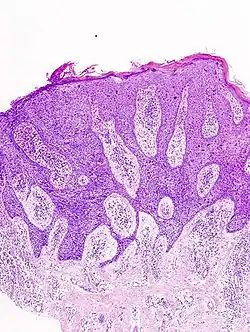

Histological characteristics

Histopathologically, the epidermis in cSCC in situ (Bowen's disease) will show hyperkeratosis and parakeratosis. There will also be marked acanthosis with elongation and thickening of the rete ridges. These changes will overly keratinocytic cells, which are often highly atypical and may have a more unusual appearance than invasive cSCC. The atypia spans the full thickness of the epidermis, with the keratinocytes demonstrating intense mitotic activity, pleomorphism, and greatly enlarged nuclei. They will also show a loss of maturity and polarity, giving the epidermis a disordered or "windblown" appearance.

Two types of multinucleated cells may be seen: the first will present as a multinucleated giant cell, and the second will appear as a dyskeratotic cell engulfed in the cytoplasm of a keratinocyte. Occasionally, cells of the upper epidermis will undergo vacuolization, demonstrating an abundant and strongly eosinophilic cytoplasm. There may be a mild to moderate lymphohistiocytic infiltrate detected in the upper dermis.[12]

Histopathology of squamous-cell carcinoma in situ (black arrow), compared to normal skin, showing marked atypia. -

Squamous-cell carcinoma in situ, showing prominent dyskeratosis and aberrant mitoses at all levels of the epidermis, along with marked parakeratosis.[12]